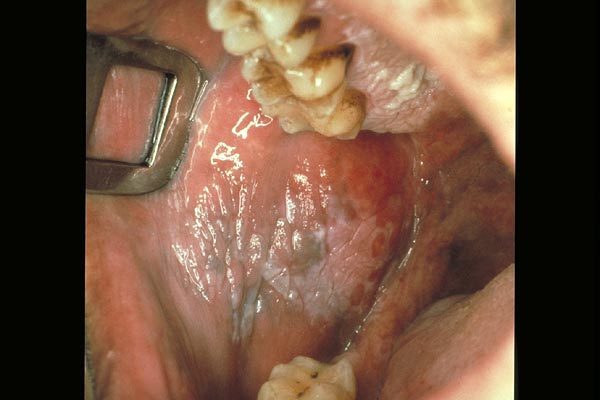

Leukoplakie

|